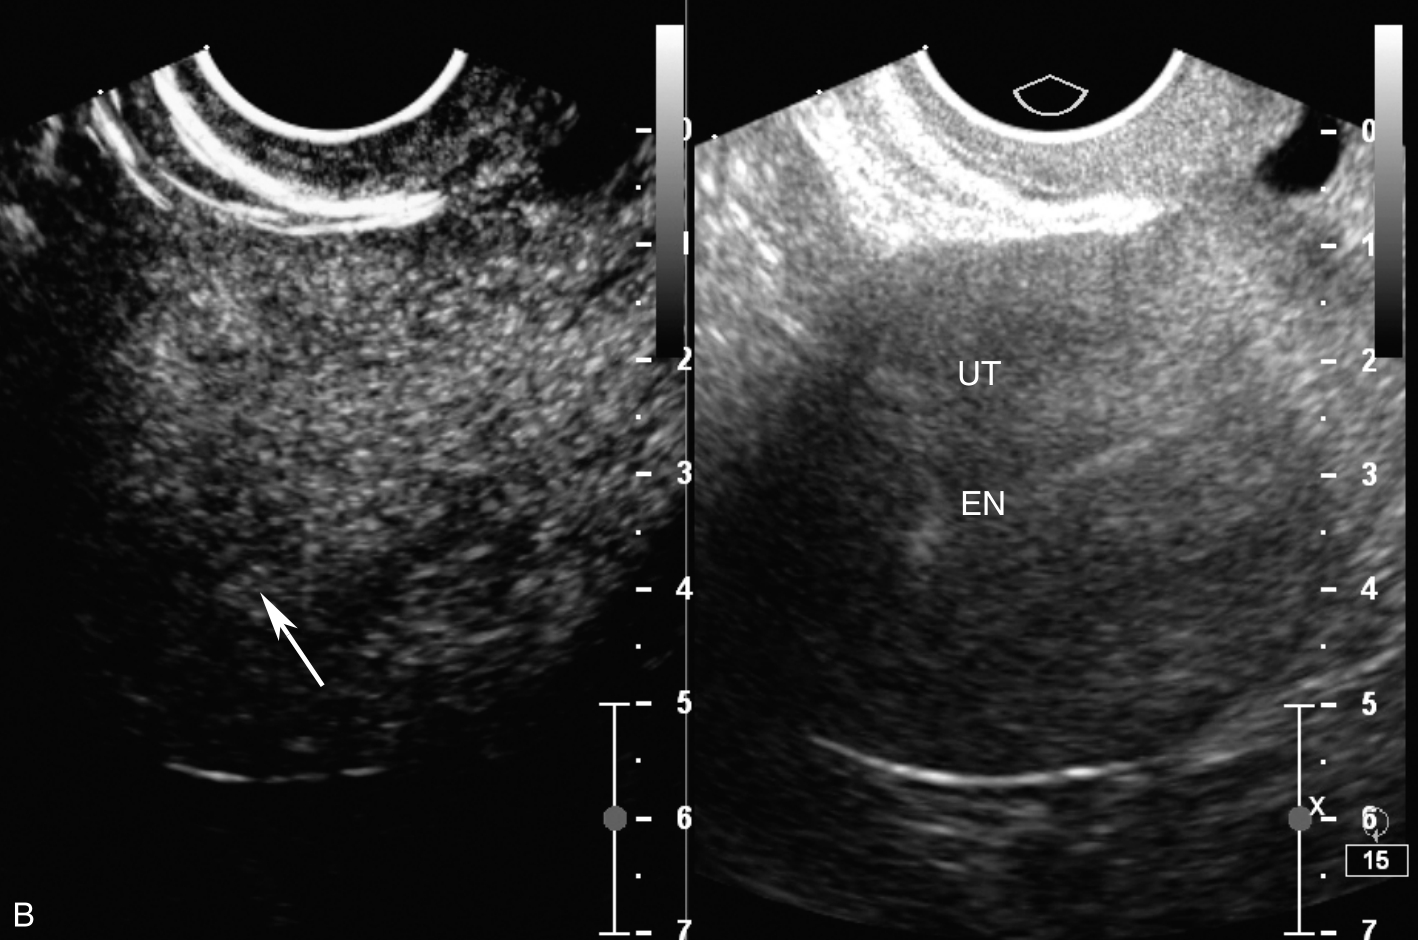

子宫经静脉超声造影见图3-12-3及ER 3-12-1。注入造影剂后16s,子宫内膜开始出现增强(图3-12-3A箭头所示),晚于子宫肌层增强;注入造影剂后23s,子宫内膜呈等增强,造影剂分布不均匀(图3-12-3B箭头所示),其周边出现造影低增强区;注入造影剂后42s,子宫肌层未见异常造影剂聚集(图3-12-3C箭头所示),子宫内膜消退与子宫肌层同步。

图3-12-3 子宫经静脉超声造影声像图

A.注入造影剂后16s;B.注入造影剂后23s;C.注入造影剂后42s。UT:子宫;EN:内膜。

子宫内膜样腺癌病灶的经静脉超声造影有如下特点:①子宫内膜增强呈“慢进同出”,未表现出高代谢的造影表现,分析可能与患者刚行宫腔诊刮且病灶仅侵及浅表肌层有关,故病灶较小且不典型;②局部内膜呈等增强,其周边出现造影低增强区,提示内膜增强不均匀;③子宫肌层未见异常造影剂聚集,提示肌壁无浸润。典型的子宫内膜癌造影表现为“快进慢出”的高增强,并可观察到内膜与子宫肌层界限不清。综上,该病例没有典型子宫内膜癌的高代谢造影表现,分析与患者刚行宫腔诊刮且病灶仅侵及浅表肌层有关。